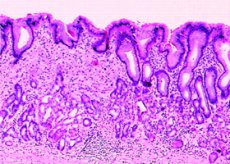

Еще одной разновидностью злокачественной опухоли является тубулярная аденокарцинома желудка. Что же она собой представляет? В первую очередь она представляет разветвленные тубулярные структуры, которые заключены в фиброзную строму или же окружены ею.

Формы опухоли весьма интересные, как правило, это клетки цилиндрические или кубические. Но в некоторых случаях они способны упрощаться за счет накопления слизи в расширенных просветах.

Тубулярный железистый рак представлен простыми или разветвленными структурами. Для нее менее характерными являются мелкоацинарные структуры типа антральных желез. Если говорить об уровне внутри- и внеклеточного слизеобразования, то он варьируется. Степень развития раковой стромы может быть различной.